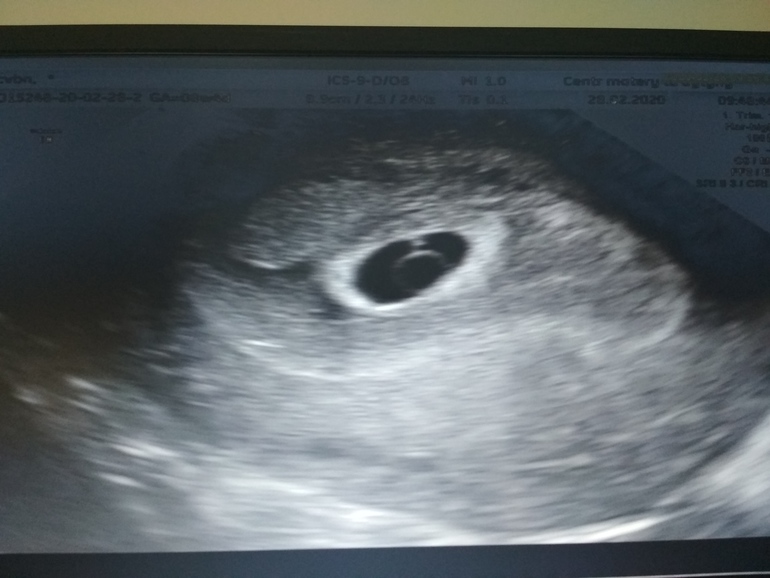

Девочки, отписываюсь. Только что с УЗИ. Мы совсем маленькие из-за поздней овуляции - 39мм, и сердечко слабенько стучит. ЖМ огромный 5,7мм, что может быть чревато замершей (так сказала врач) Да ещё и гематома шикарная 8*9,3. Написали соответствует 6нед+1д. УЗИ через неделю контрольное.